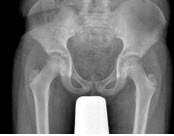

46、单项选择题

女,根据其正常骨盆影像图像,判断其最可能的年龄()

A.69岁左右

B.59岁左右

C.49岁左右

D.19岁左右

E.39岁左右